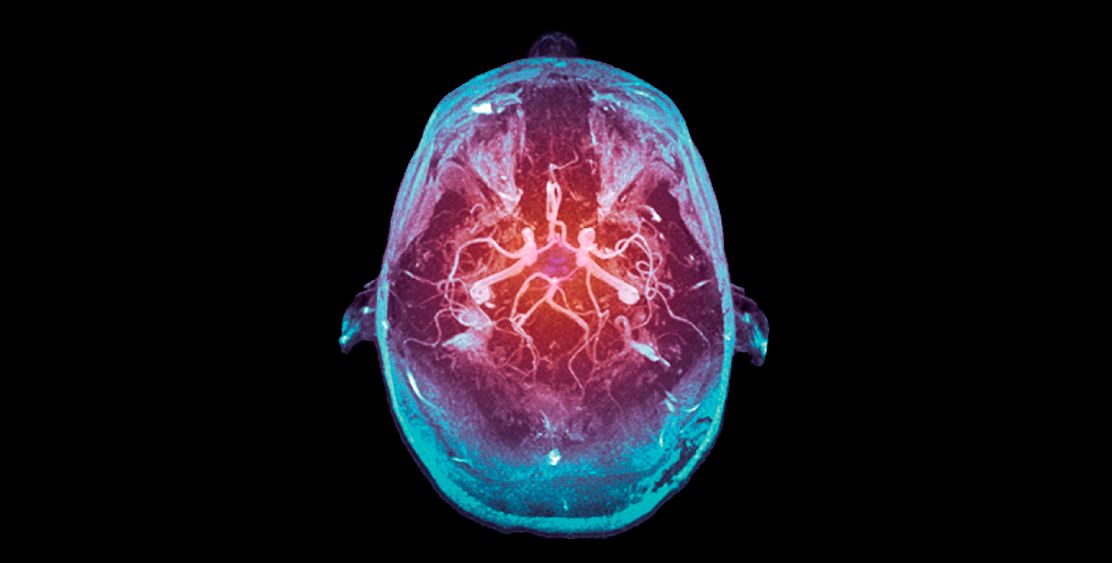

Cerebral circulation

The importance of knowing the vascularization system is the relation that keeps to diagnose a CVD or some other pathology. It is this system that will provide oxygen and blood to the brain if any obstruction occurs at the level of any structure that composes it. The blood supply would decrease, and the patient's life would play a very important role, where time is a vital factor.

Unlike most organs, whose vascularization system is based on a single vascular pedicle, the brain has a special irrigation composed of four large arteries that form two large well-differentiated vascular systems:

The vertebral arteries fuse intracranially formed a trunk known as the basilar artery. In the following image you can see the emphasis on the regions that irrigate the carotid and vertebrobasilar system: